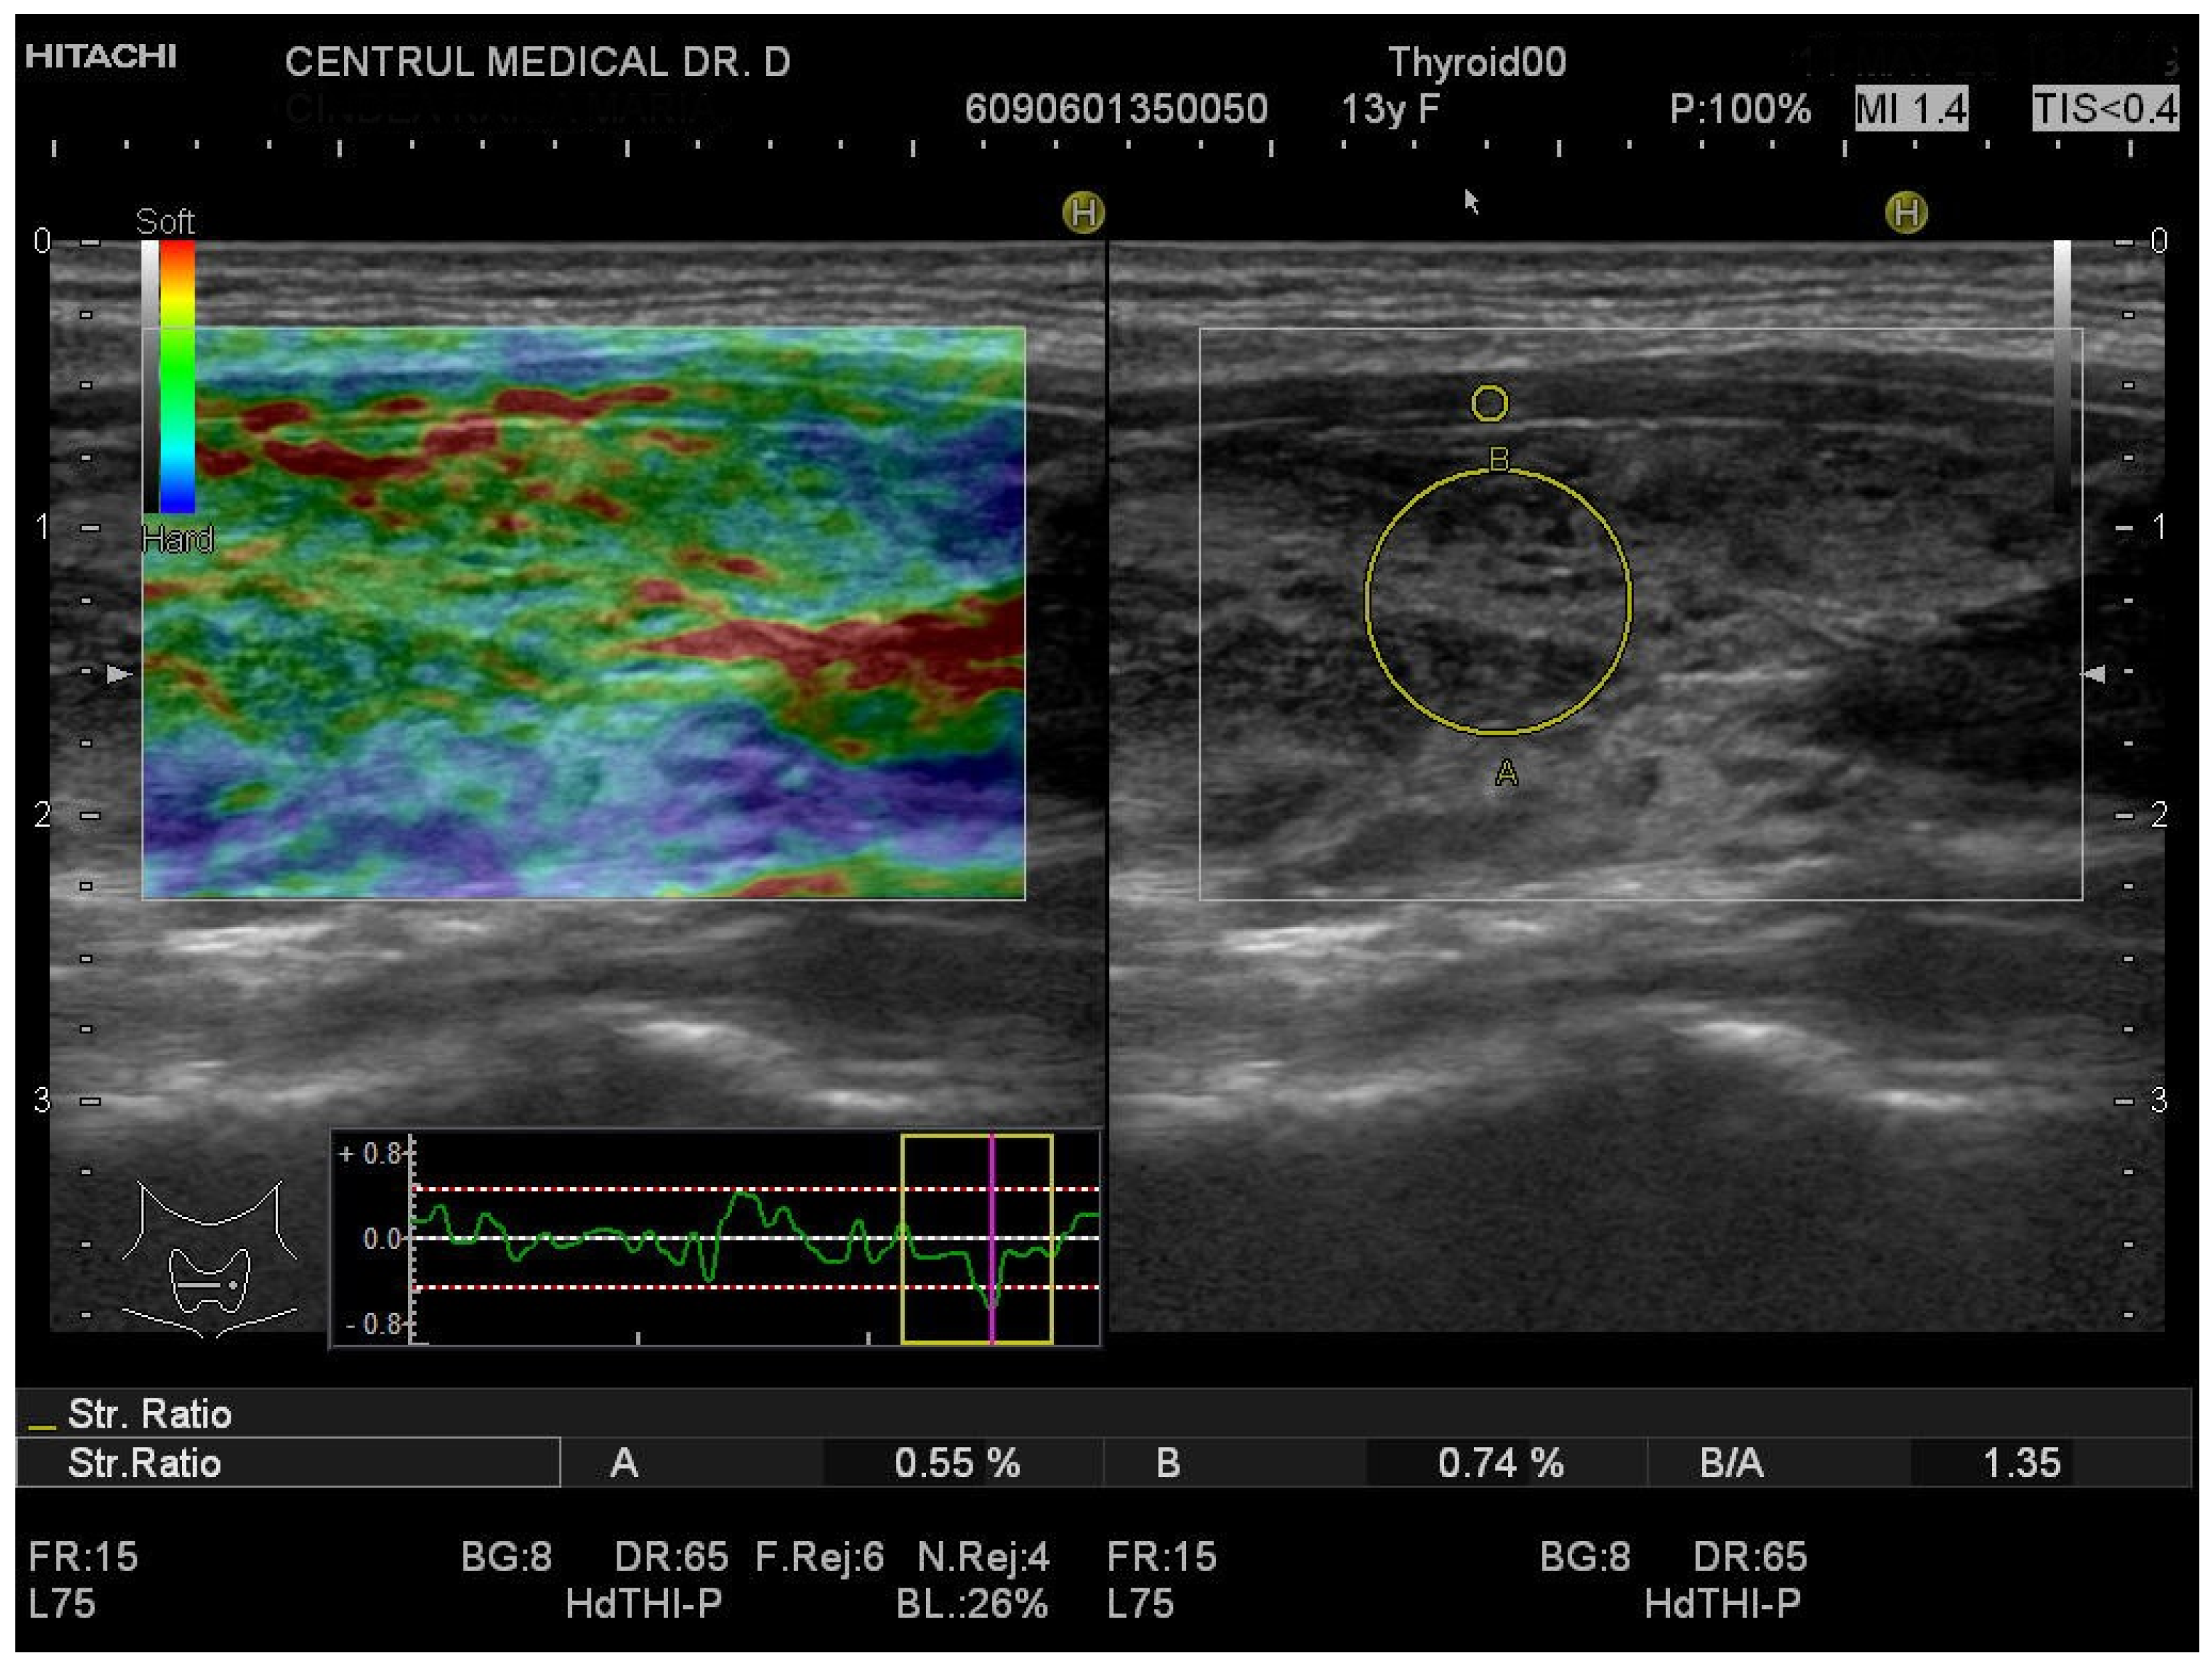

3.1. Strain Elastography Measurements

| SE | SR-THY | 1.2 (1.2–1.3) | 0.7 (0.6–0.9) | <0.0001 |

| SR-LL | 1.3 (1–1.5) | 0.7 (0.5–0.8) | <0.0001 | |

| SR-RL | 1.2 (1–1.4) | 0.7 (0.6–1) | <0.0001 | |